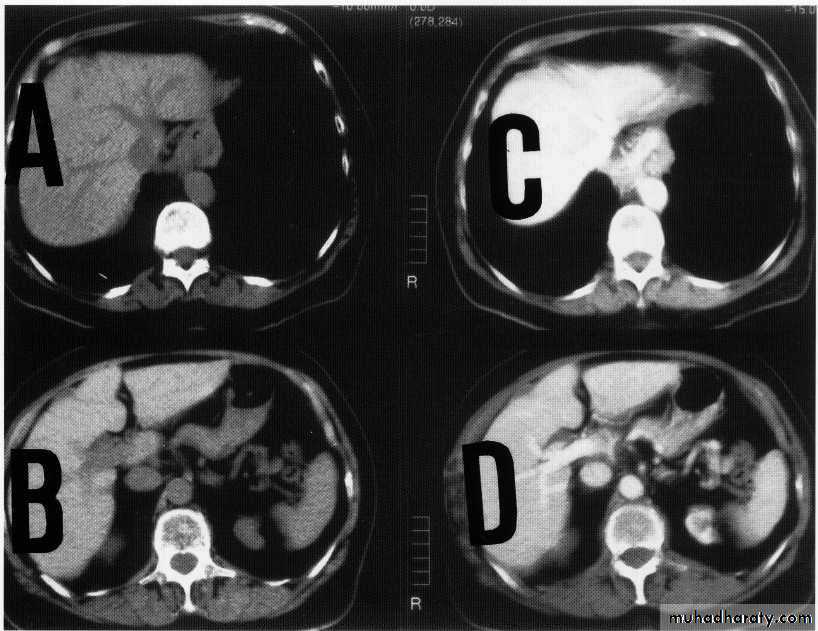

hepatic mets

hepatic mets,arterial phase

hepatic mets venous phase